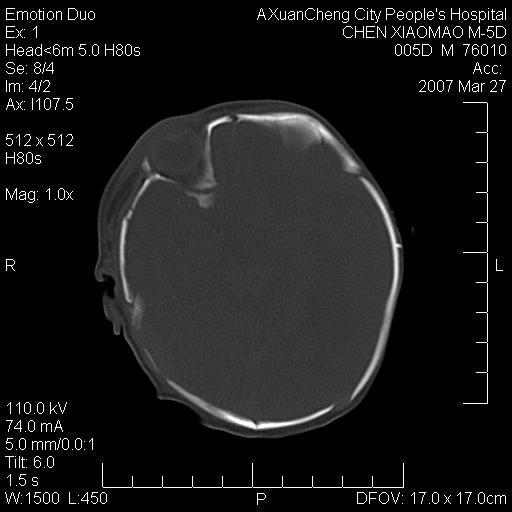

大家看看可有出血?另外枕骨中央是骨缝还是骨折

颅内未见明显异常。枕骨鳞部应为假缝(颅外软组织无肿胀),有外伤吗?

左颞枕部有出血,枕骨有骨折

枕骨骨折可以下,应该比较明显,颅内还是正常的,不放心的话,短期随访。

未见明显异常,,那是横窦影,“缝”是后囟